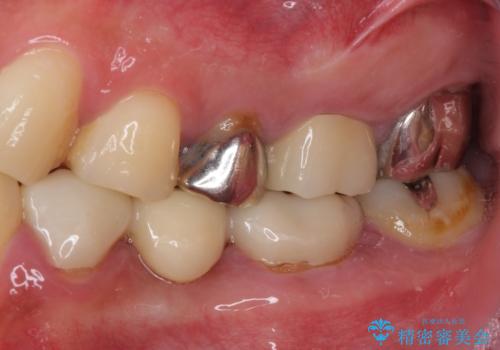

- 奥歯が痛いとのことで来院された患者様です。

歯肉に排膿の痕があり、叩いたり咬んだりすると痛みを感じていました。

根管治療を行い、その後フルジルコニアクラウンにて補綴することとしました。